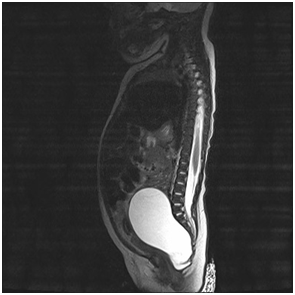

Our assessment revealed a healthy baby girl with a large fixed supra pubic mass which was tender to palpation. The urinary catheter was in situ and draining clear urine. Per rectal examination was done, the mass was easily palpable at pre sacral area. An urgent ultrasound abdomen was performed; it revealed a cystic mass in the pelvis 10cm x 5cm; (larger than previously documented radiologically), no calcification was noted, there was also mild right hydronephrosis. An MRI was carried out to enable us to differentiate between anterior meningocoele and a sacrococcygeal teratoma. The MRI showed a large pre-sacral cystic mass consistent with an intra-pelvic teratoma (Figure 1). Her Alpha-fetoprotein (AFP) was 3746 unit (normal range 0.00 – 6.74). BHCG 4.2 IU/L (normal range < 5 IU/L). Her renal profile was also normal.